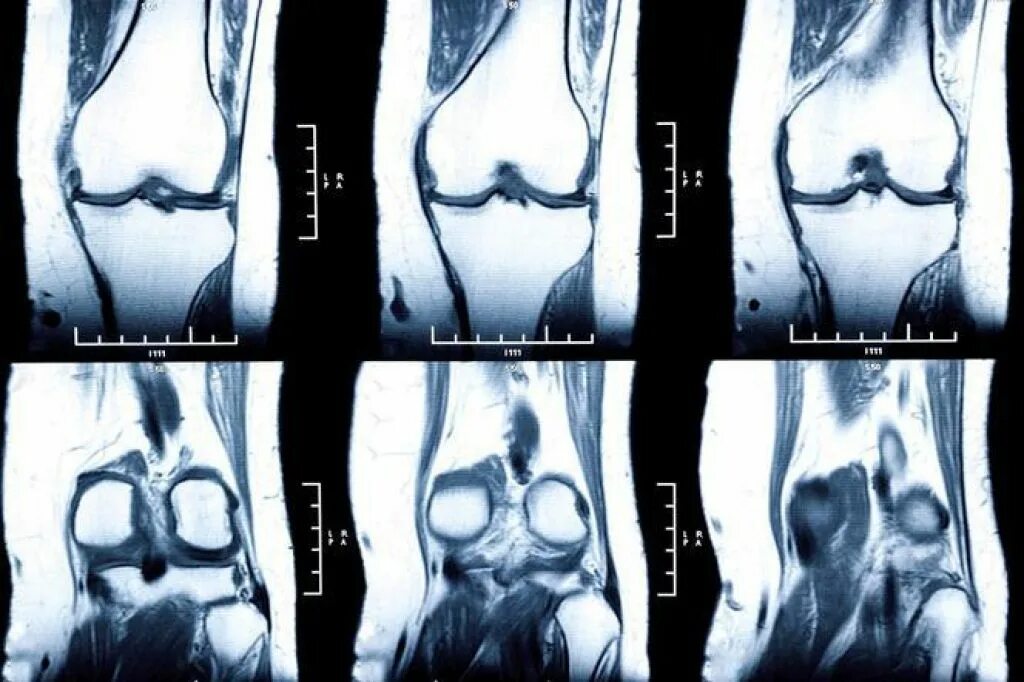

Мрт коленного сустава набережные